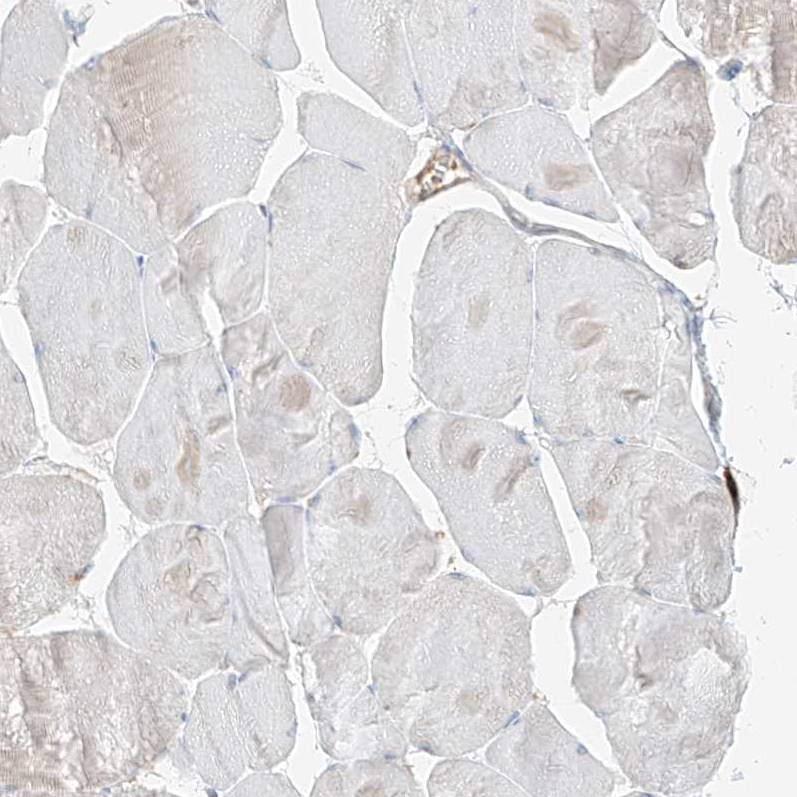

Immunohistochemical staining of human testis shows moderate cytoplasmic positivity in Leydig cells.